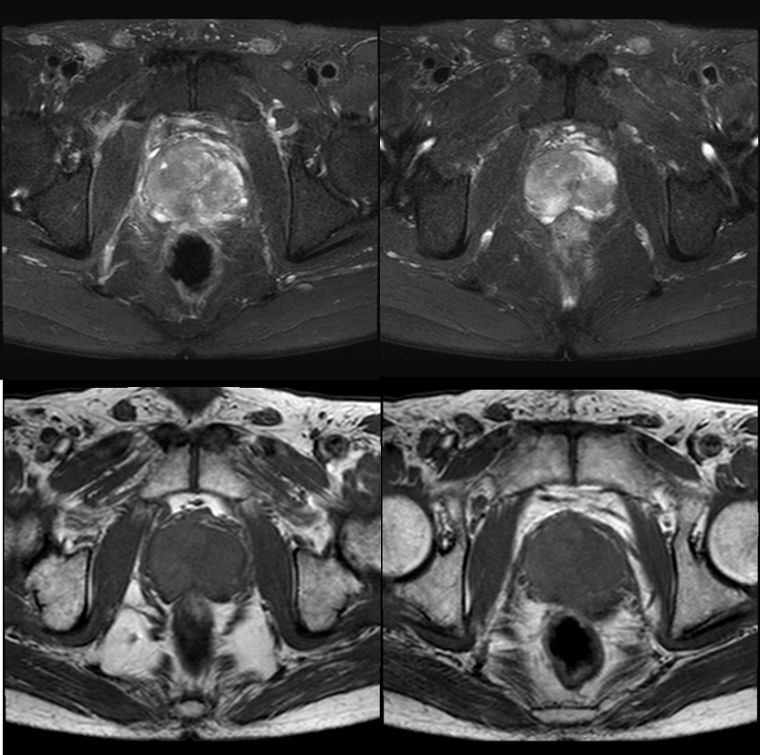

MR

2018.6影像表现如下:

前列腺外周带及中央腺体异常信号灶,前列腺癌待排,累及右侧精囊腺。盆腔及两侧腹股沟肿大淋巴结。